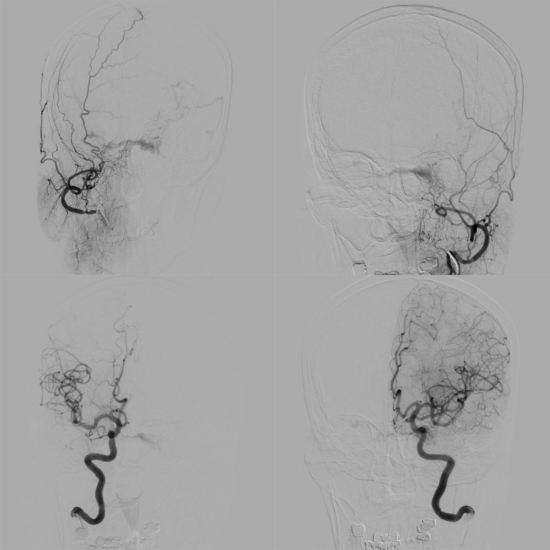

术前造影显示双侧颈内动脉、颈外动脉分支供血的硬脑膜动静脉瘘